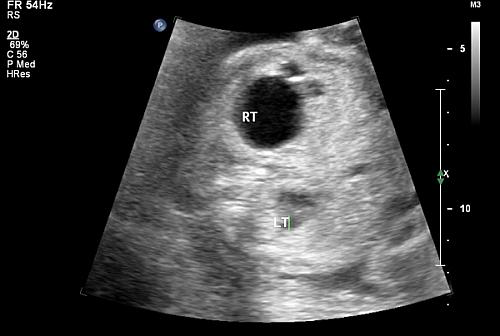

در سونوگرافی پزشک به موارد زیر توجه می کند:

- وجود هیدرونفروز در یک یا هر دو کلیه

- شدت هیدرونفروز

سلام، در سونو غربالگری دوم مشخص شد جنین ورم خفیف ۵.۲ در کلیه چپ و ۵.۱ در کلیه راست داره، در سونو هفته ۲۶ ورمی در کلیه راست دیده نشد اما ورم کلیه چپ به ۱۳.۳ mm رسید. حجم مایع آمنیوتیک نرمال و ۱۳ cm است. دکتر دستور انجام سونو برای یک ماه دیگه را داده، میخواستم نظر پزشک محترم را بدونم که آیا انجام زایمان زودرس و جراحی نوزاد بعد از تولد در چنین حالتی، اجتناب ناپذیره؟

سونوگرافی در هفته ۲۰

کلیه راست دیامتر ۵م م وکلیه چپ دیامتر کلیه چپ ۸ م م

ودرسونوگرافی هفته ۲۸

دیامتر لنگچه کلیه راست ۱۲م م ضخامت کورتکس آن ۳ م م

ودیامترلنگچه چپ ۲۶ م م وضخامت کورتکس آن ۱م م